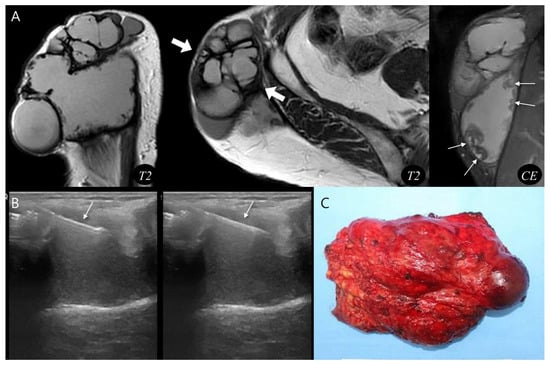

Pseudoaneurysm Versus Chronic Expanding Hematoma on MRI: Hematoma-like Lesions with Distinct Therapeutic Strategies

by

Seul Ki Lee, Jun-Ho Kim and Jee-Young Kim

Biomedicines 2025, 13(11), 2834; https://doi.org/10.3390/biomedicines13112834 - 20 Nov 2025

Background/Objectives: Pseudoaneurysm and chronic expanding hematoma (CEH) are uncommon soft tissue lesions that can mimic hematoma or hemorrhagic tumors on magnetic resonance imaging (MRI). Because treatment strategies differ, accurate differentiation is important. This study aimed to compare MRI characteristics of pseudoaneurysm and CEH

Background/Objectives: Pseudoaneurysm and chronic expanding hematoma (CEH) are uncommon soft tissue lesions that can mimic hematoma or hemorrhagic tumors on magnetic resonance imaging (MRI). Because treatment strategies differ, accurate differentiation is important. This study aimed to compare MRI characteristics of pseudoaneurysm and CEH and identify distinguishing imaging features. Methods: We retrospectively reviewed 12 patients diagnosed between June 2010 and June 2023 with pseudoaneurysm (n = 6) or CEH (n = 6). Patient demographics, lesion depth, and size were compared. MRI features were evaluated for morphology, internal characteristics, pulsatile artifact, and involvement of adjacent structures. Results: Pseudoaneurysms were consistently located in the muscle layer, whereas CEHs were predominantly found in the subcutaneous fat layer (83.3%, p = 0.015). CEHs were significantly larger than pseudoaneurysms (13.5 ± 3.9 cm vs. 6.1 ± 3.3 cm, p = 0.005). Pseudoaneurysm more frequently exhibited ovoid morphology (100%), central flow void on T1WI and T2WI (100%), inner peripheral high SI on T1WI (83.3%), and neurovascular bundle involvement (100%) (all p < 0.05), while CEHs demonstrated multilobular morphology (100%) and internal septations (83.3%) (p < 0.05). Conclusions: Lesion location, size, morphology, central flow void, inner peripheral high T1 signal, septation, and neurovascular involvement enables reliable MRI differentiation between pseudoaneurysm and CEH, guiding accurate diagnosis and guiding appropriate management.